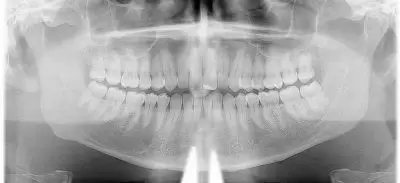

Ortopantomografía

Es una prueba radiográfica gracias a la cual obtenemos una imagen completa de los dientes, maxilares y estructuras anatómicas adyacentes. Es nuestra herramienta diagnóstica de primer orden.

Su uso es de gran relevancia en las primeras visitas, pues nos da una visión general del estado de salud oral del paciente.

Esta prueba se aconseja a partir de los 6 años de edad; momento en el que podemos observar si todos los dientes que faltan por salir están donde deben de estar y controlar así la erupción de recambio, de temporal a dentición definitiva, más rigurosamente a nuestros pacientes más pequeños.